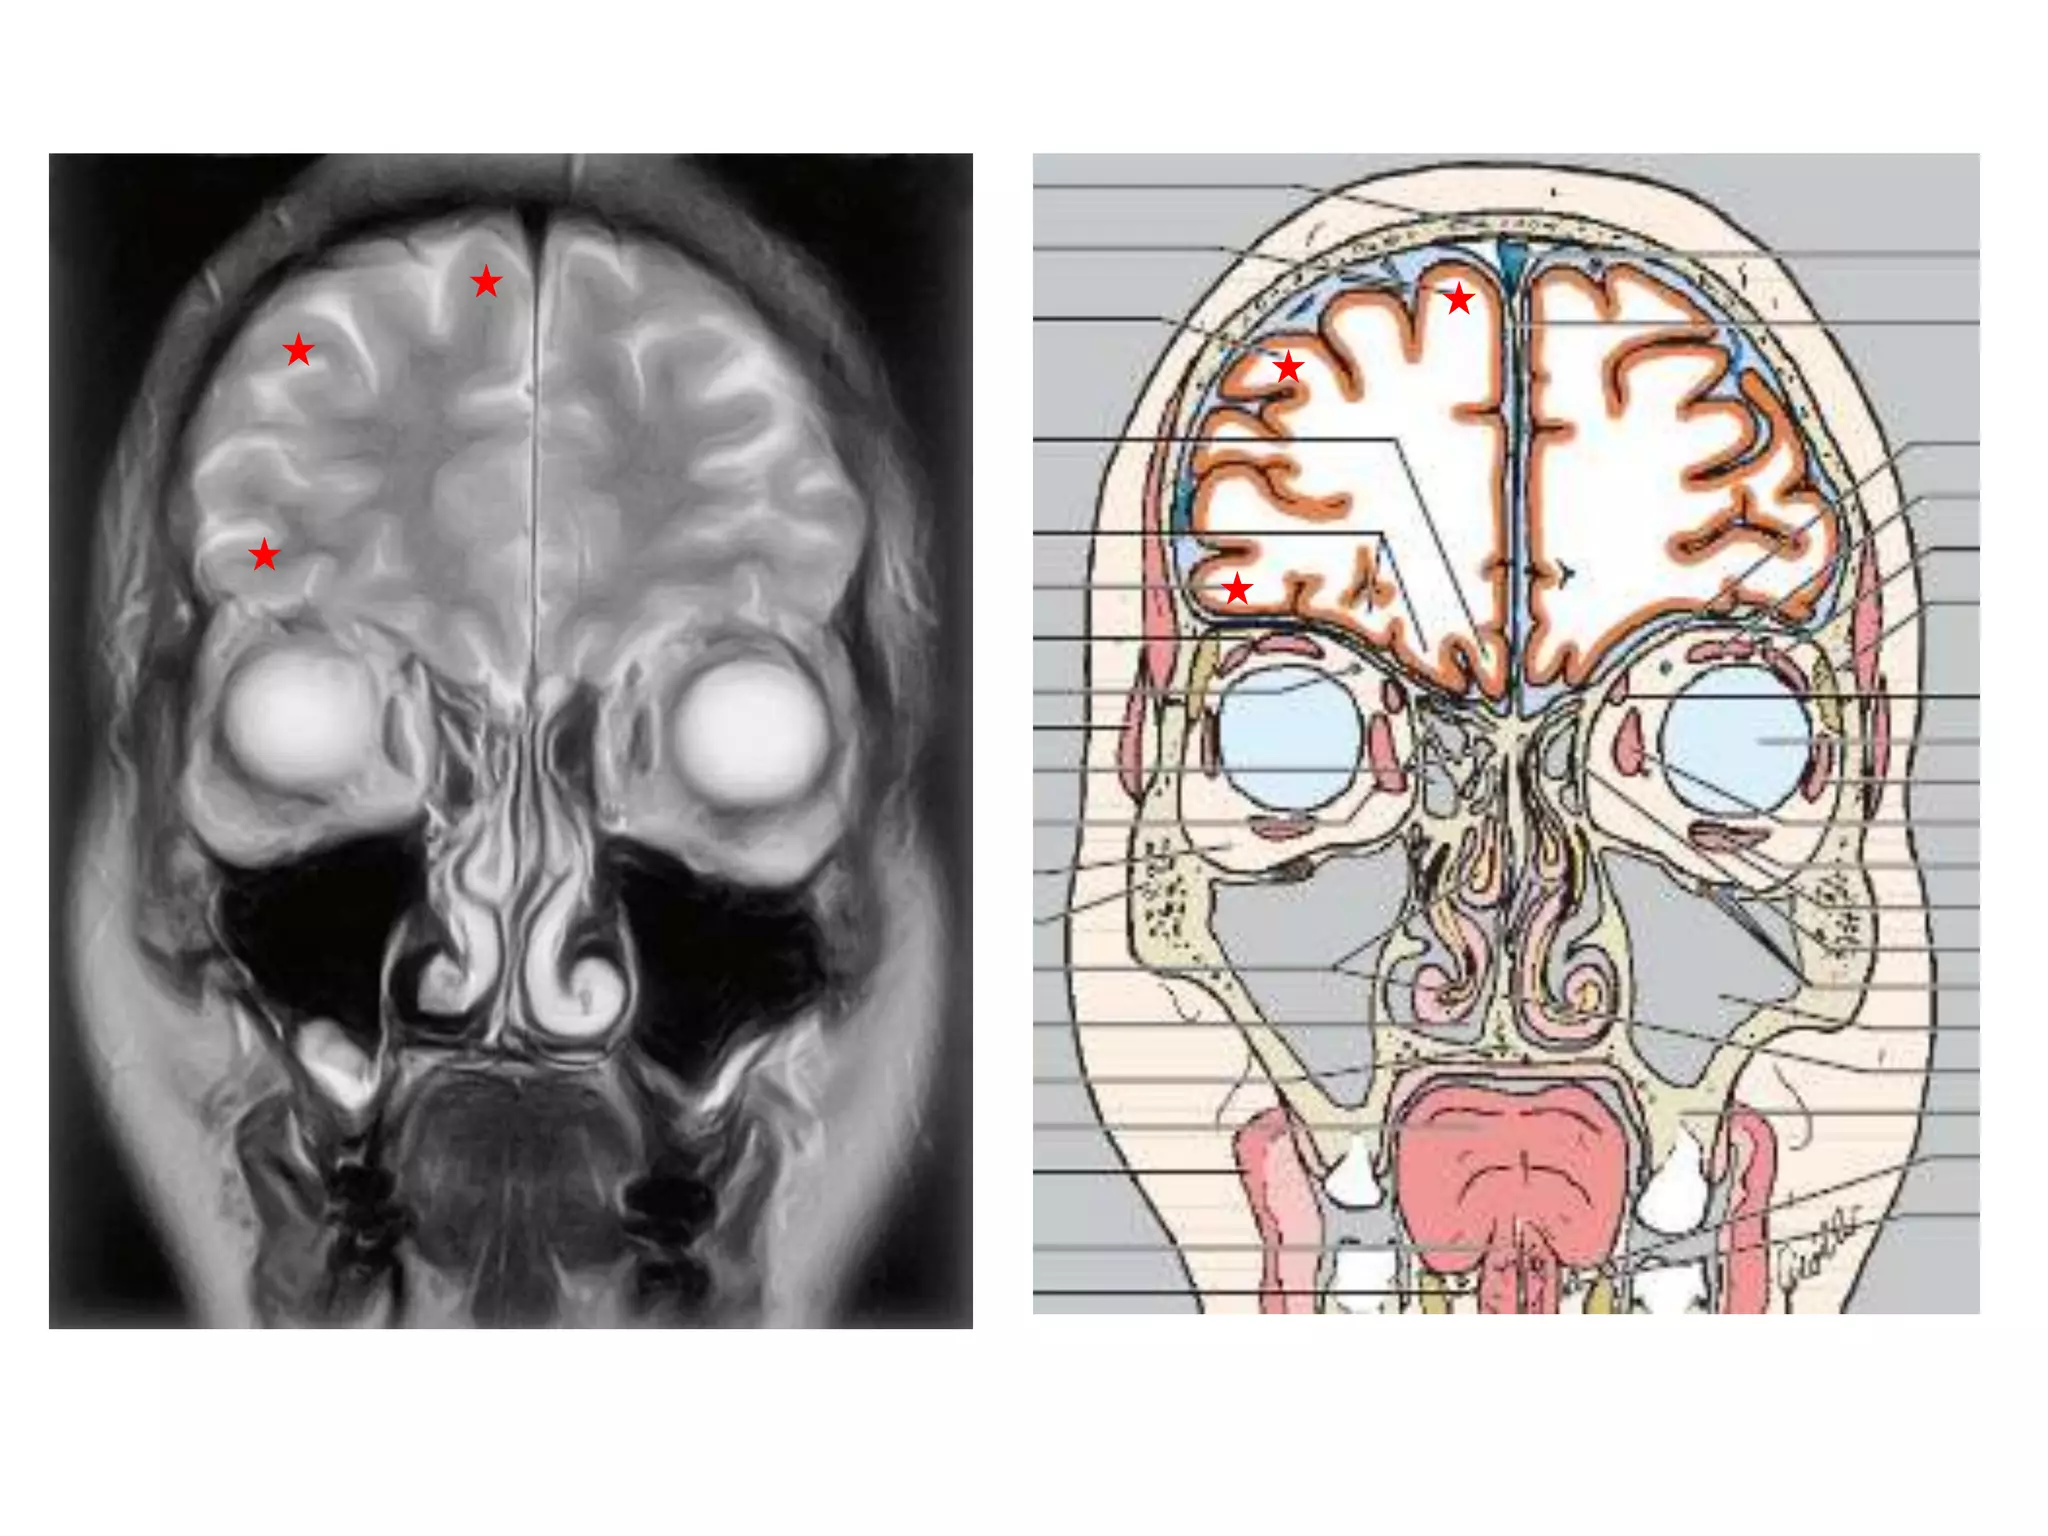

CEREBRAL HEMISPHERES

• 4 lobes are present in each hemisphere. They are

demarcated by fissures.

• Each lobe is again divided into gyri by sulci . They are

named accordingly.

• Anatomy of cerebral hemispheres and mid brain – T1 W

MRI.

• Internal grey - white matter areas – T2 W MRI.

• In Cerebral hemispheres , white matter above the level of

lateral ventricles is called centrum semiovale

FISSURES

1. Central sulcus

2. Sylvian fissure

3. Calcarine sulcus (temporo-occipital fissure)

4. Parieto-occipital fissure :

Seen medially. Better seen on midline saggital MRI.